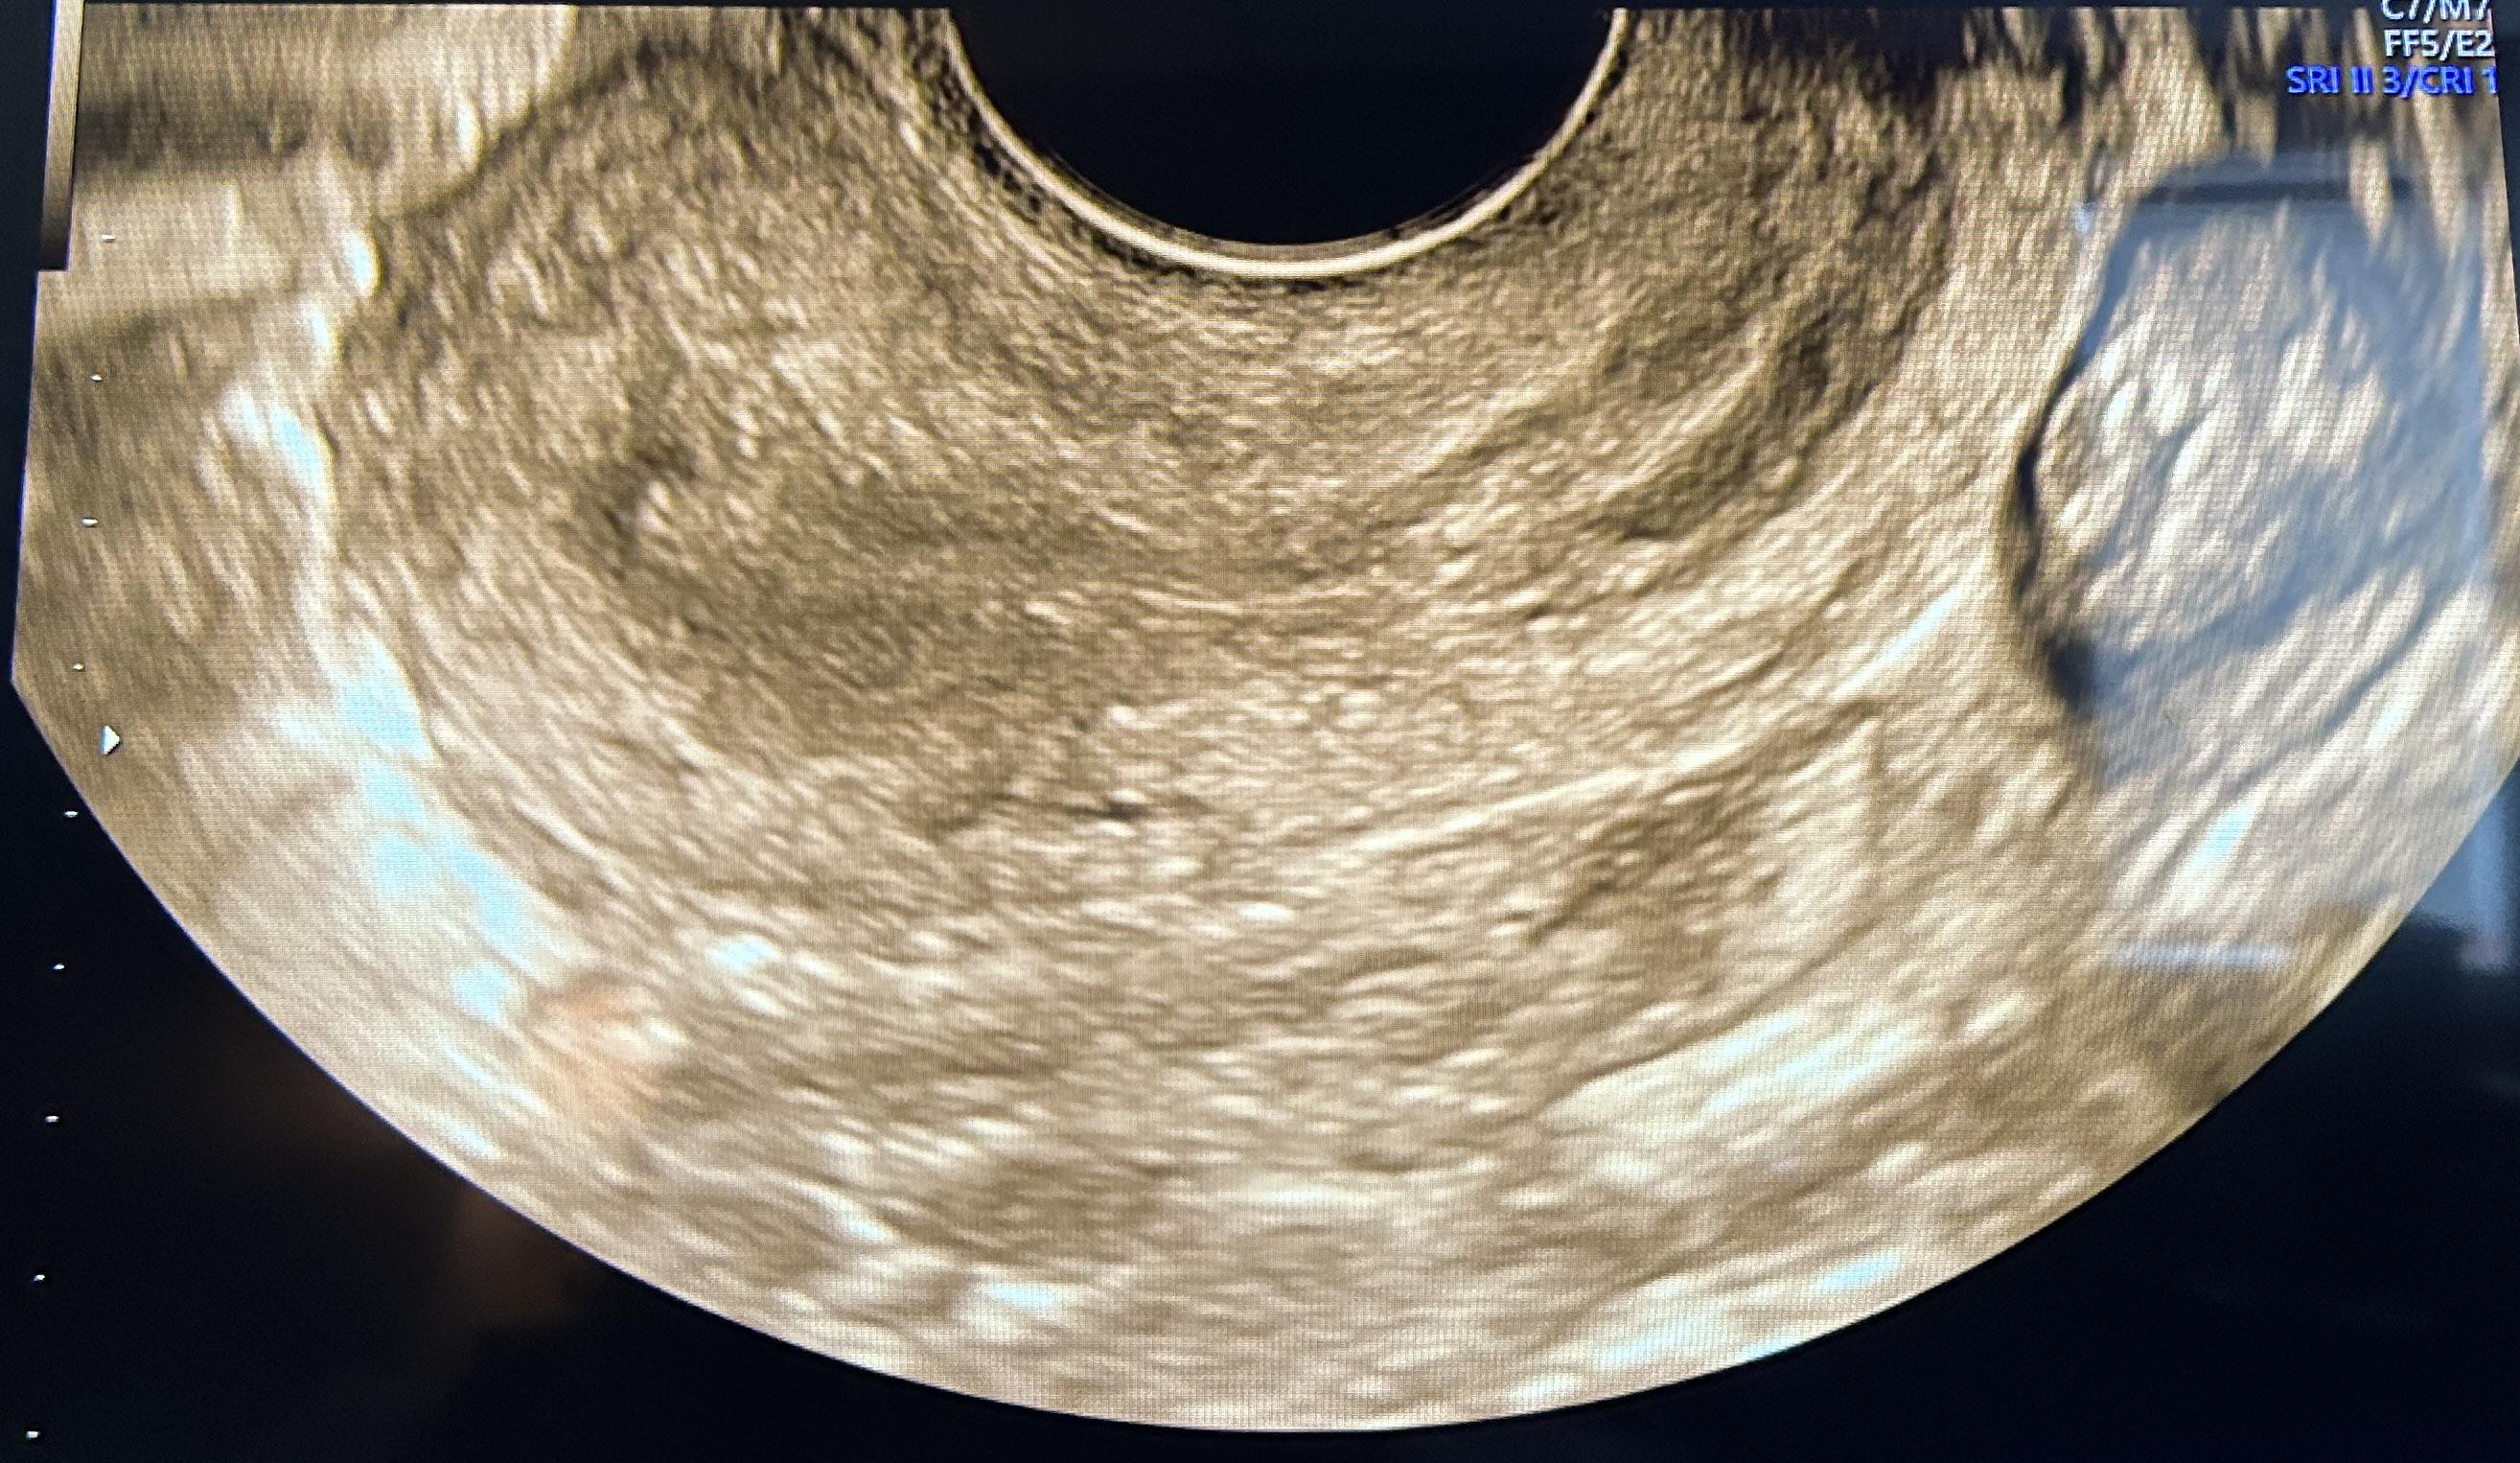

Normal Ovary Ultrasound

Discover how an ovarian cancer ultrasound serves as a vital diagnostic tool for early detection. Learn about transvaginal ultrasound imaging, the role of pelvic exams, and how specialists interpret pelvic masses to assess potential malignancy. Understand the imaging procedures and accuracy of ultrasound technology in identifying ovarian abnormalities to ensure timely medical intervention and improved patient outcomes.

TitleNormal Ovary Ultrasound

Read full article: Ovarian Cancer Ultrasound